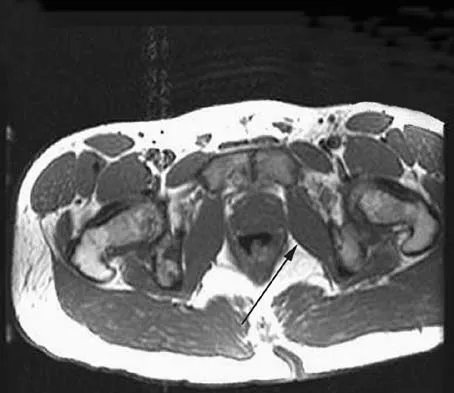

A 73-year-old woman reports a 4-month history of severe left-sided posterior buttock pain and left leg pain. The leg pain radiates into the left lateral thigh and posterior calf with cramping. Examination reveals mild difficulty with a single-leg toe raise on the left side and a diminished ankle reflex. There is also a significant straight leg raise test at 45 degrees which exacerbates symptoms. An MRI scan is shown in Figure 4. What is the most appropriate treatment at this time?

Lumbar spinal stenosis with lumbar radiculopathy can be commonly caused by a synovial cyst arising from the facet joints. Lyons and associates reported on the surgical treatment of synovial cysts in 194 patients. Of the 147 with follow-up data, 91% reported good pain relief and 82% had improvement of their motor deficits. Epstein reported a 58% to 63% incidence of good/excellent results and a 38 to 42 point improvement on the SF-36 Physical Function Scale. It was also suggested that since the presence of a synovial cyst indicates facet pathology, possible fusion should be considered in these patients, especially those with underlying spondylolisthesis. Lyons MK, Atkinson JL, Wharen RE, et al: Surgical evaluation and management of lumbar synovial cysts: The Mayo Clinic Experience. J Neurosurg 2000;93:53-57. Khan AM, Synnot K, Cammisa FP, et al: Lumbar synovial cysts of the spine: An evaluation of surgical outcome. J Spinal Disord Tech 2005;18:127-131.